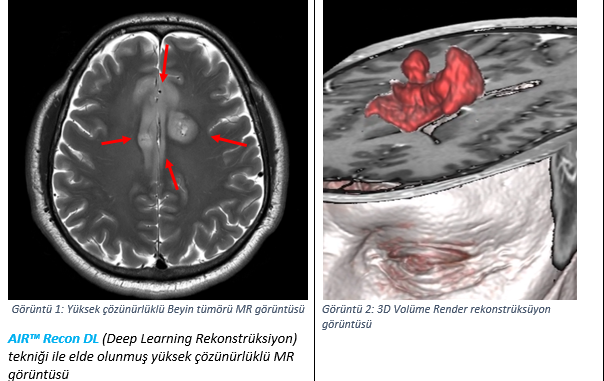

Karaarslan'ın Radyoloji Klinik Direktörü olduğu Maslak Acıbadem Hastanesi'nde de kullanılan, GE Sağlık'ın üst düzey 3 Tesla manyetik rezonans görüntüleme sistemi SIGNA Premier, yapay zeka ve derin öğrenme özellikleri ile birlikte; MR görüntülemenin ikilemi olan sorunun çözülmesine, yani; görüntü kalitesinin artırılmasına ve çekim süresinin kısaltılmasına eş zamanlı olarak katkı sunuyor.